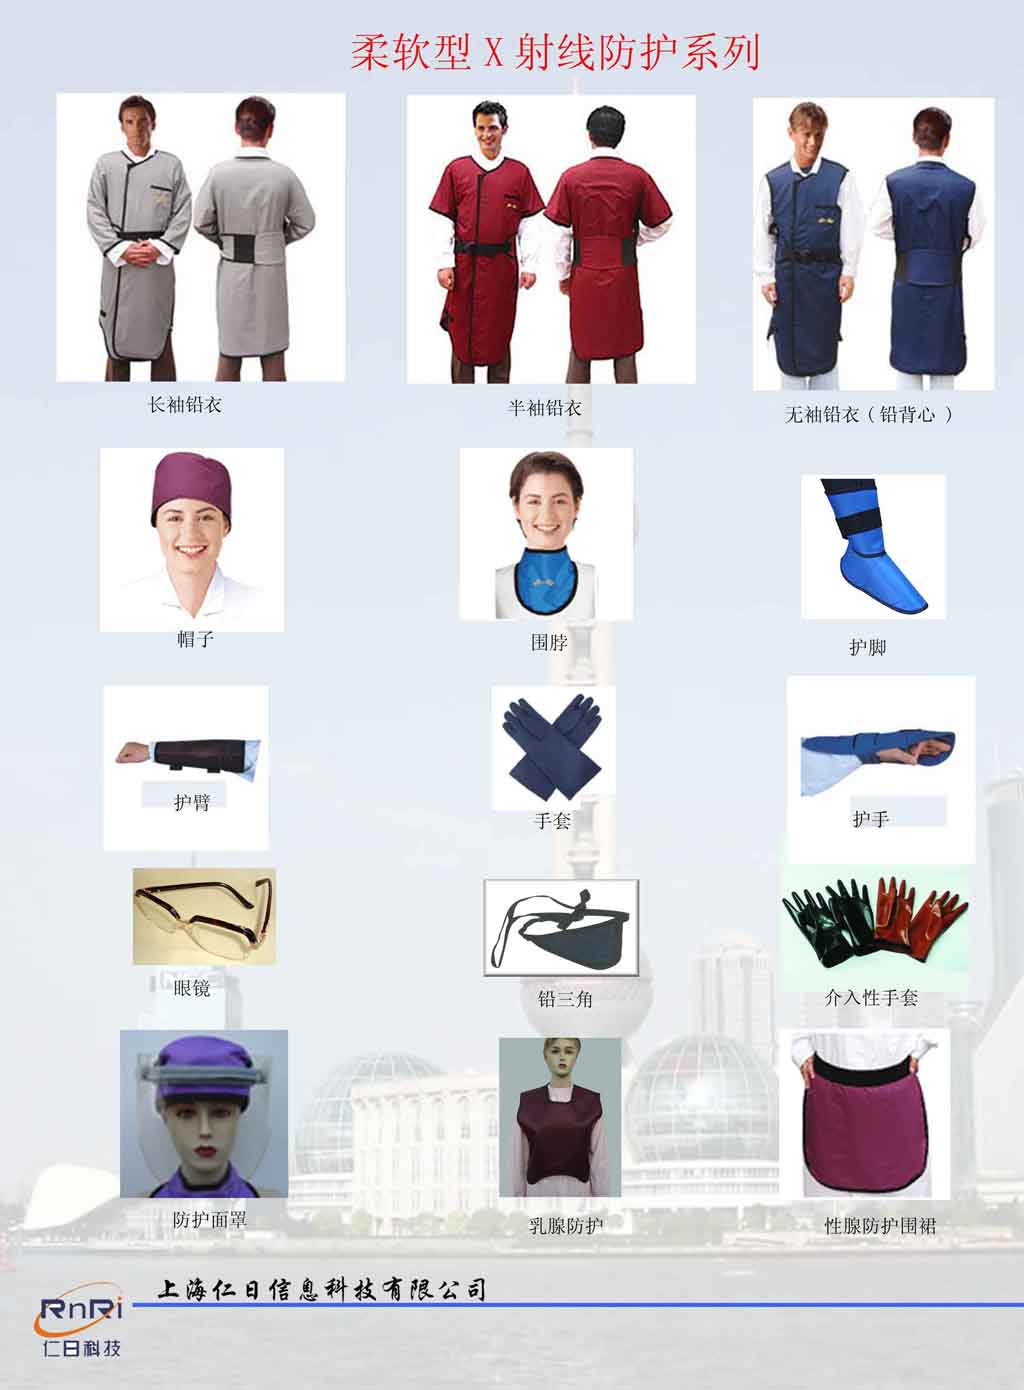

�aƷ���Q��X�侀���o�U��,�U��,�Uȹ,�Uñ,�U���R,�U����,�U�_�ס��U�^��

�aƷ������һ���L�䡢���䡢�o���侀���o�� 1�����o�UƤ����ܛ���o���ϣ� 2�����o���ܼѣ��U�ֲ������ṩ0.35/0.5mmPb�U������ ��ĥ������ϴ������� 3���Y���OӋ�����ö��Ӳ������������ό��I�����Ի��Y���OӋ�����������m�� 4�� ����������ˇ��������